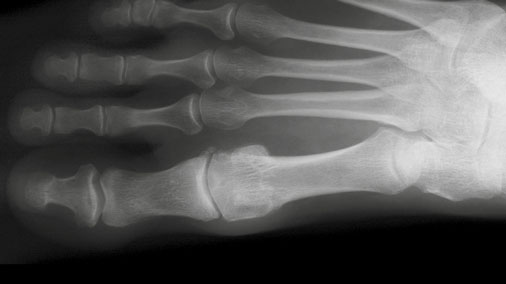

Cheilektomie: schematische Darstellung von der Seite

Cheilektomie: Hallux rigidus nach Operation im Röntgenbild

Bei der Cheilektomie kommt es zur Abtragung von knöchernen Anbauten und von bewegungsbehindernden Gelenkanteilen, so dass die Beweglichkeit des Gelenks wieder verbessert wird. Dieses Verfahren kann nur im Frühstadium der Arthrose angewendet werden.